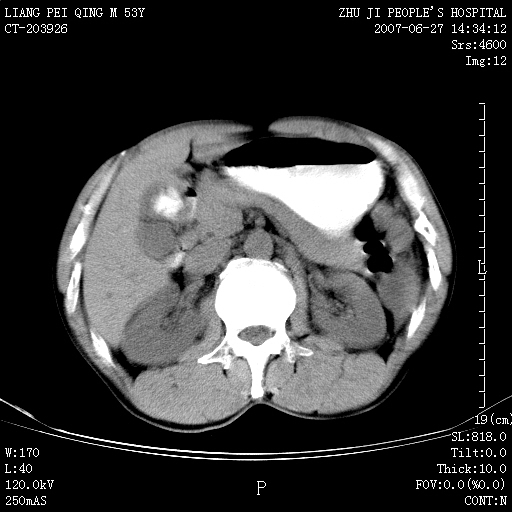

以下是引用余辉在2007-6-27 18:46:00的发言:[br]病灶多发,内可见大片状低密度区,病灶病灶等密度区轻度强化,动脉期后期病灶低密度区与高密度区对度增加,考虑1淋巴瘤2转移瘤3血管内皮细胞瘤(不知有否静脉期及延迟期扫描)

以下是引用zzzzhhhhaaaannnn在2007-6-27 20:44:00的发言:[br]脾脏 肋骨转移可能性大,下腔静脉内有癌栓

以下是引用狙击手在2007-6-28 10:35:00的发言:[br]1:定位:来源于脾脏。2:强化:强化,但不均匀。3:下腔静脉癌栓?下腔静脉充填不均匀与增强时间有关,延时即可明确。4:肋骨破坏?看起来并不确切。综上考虑几个最常见诊断:1;淋巴管瘤;2;血管内皮肉瘤(高度恶性,早期即可转移,常见肝,肺,骨)3;转移瘤(无特征性,只有肝或其它腹腔脏器有类似病变时,才可提示之)